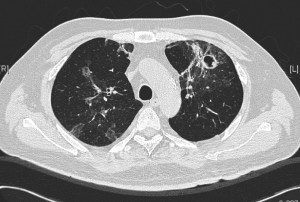

This is the same middle-aged man presented in the previous clinical vignette. He had undergone allogeneic stem cell transplantation (allo-HSCT) for underlying B-cell leukemia, with subsequent acute graft-versus-host disease (GVHD) of the liver. This was complicated 6 months later by RSV pneumonitis as previously described. His recovery was slow and required oxygen support even 3 weeks after the start of the RSV infection. A repeat CT showed cavities in both lung fields, with resolution of the prior ground-glass changes. These cavities appeared in the regions of the lungs previously affected by RSV. He was otherwise afebrile, with a slight cough and exertional dyspnea (requiring oxygen support) but has no other symptoms.

The repeat CT thorax showed multiple irregular, thick-walled cavities in both lungs. Medscape has a nice article on the various differentials of cavitary lung lesions. Various bacterial, fungal and mycobacterial organisms are able to cause such changes in an immunocompromised patient, but the most likely cause in this particular setting is infection caused by a mould belonging to Aspergillus spp. This can be diagnosed indirectly via serum or broncho-alveolar lavage fluid testing for galactomannan – a component of the Aspergillus spp. fungal cell wall (although the former is not particularly sensitive), or biopsy of the wall of a cavity. Treatment upon confirmation of diagnosis is with antifungal therapy. Voriconazole is currently the drug of choice – amphotericin formulations are only available via the intravenous route and the liposomal formulations are generally extremely expensive with equivalent or poorer outcomes compared to voriconazole.